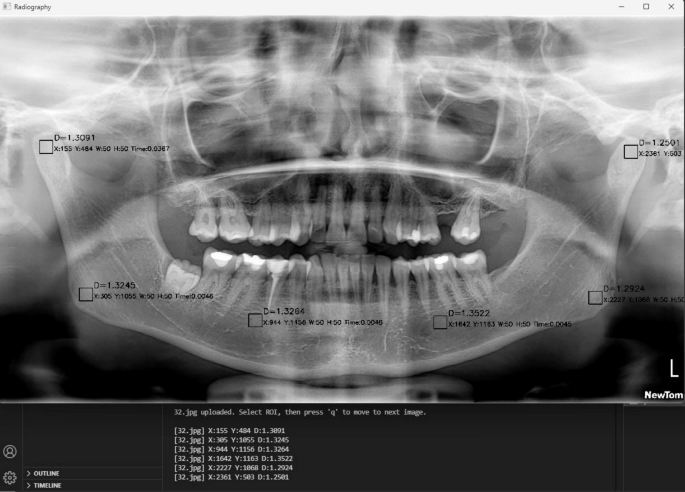

This study investigated mandibular trabecular bone architecture in individuals with T1DM using a newly developed single-click fractal analysis module on panoramic radiographs. The findings revealed significantly higher FD values in the gonial and…